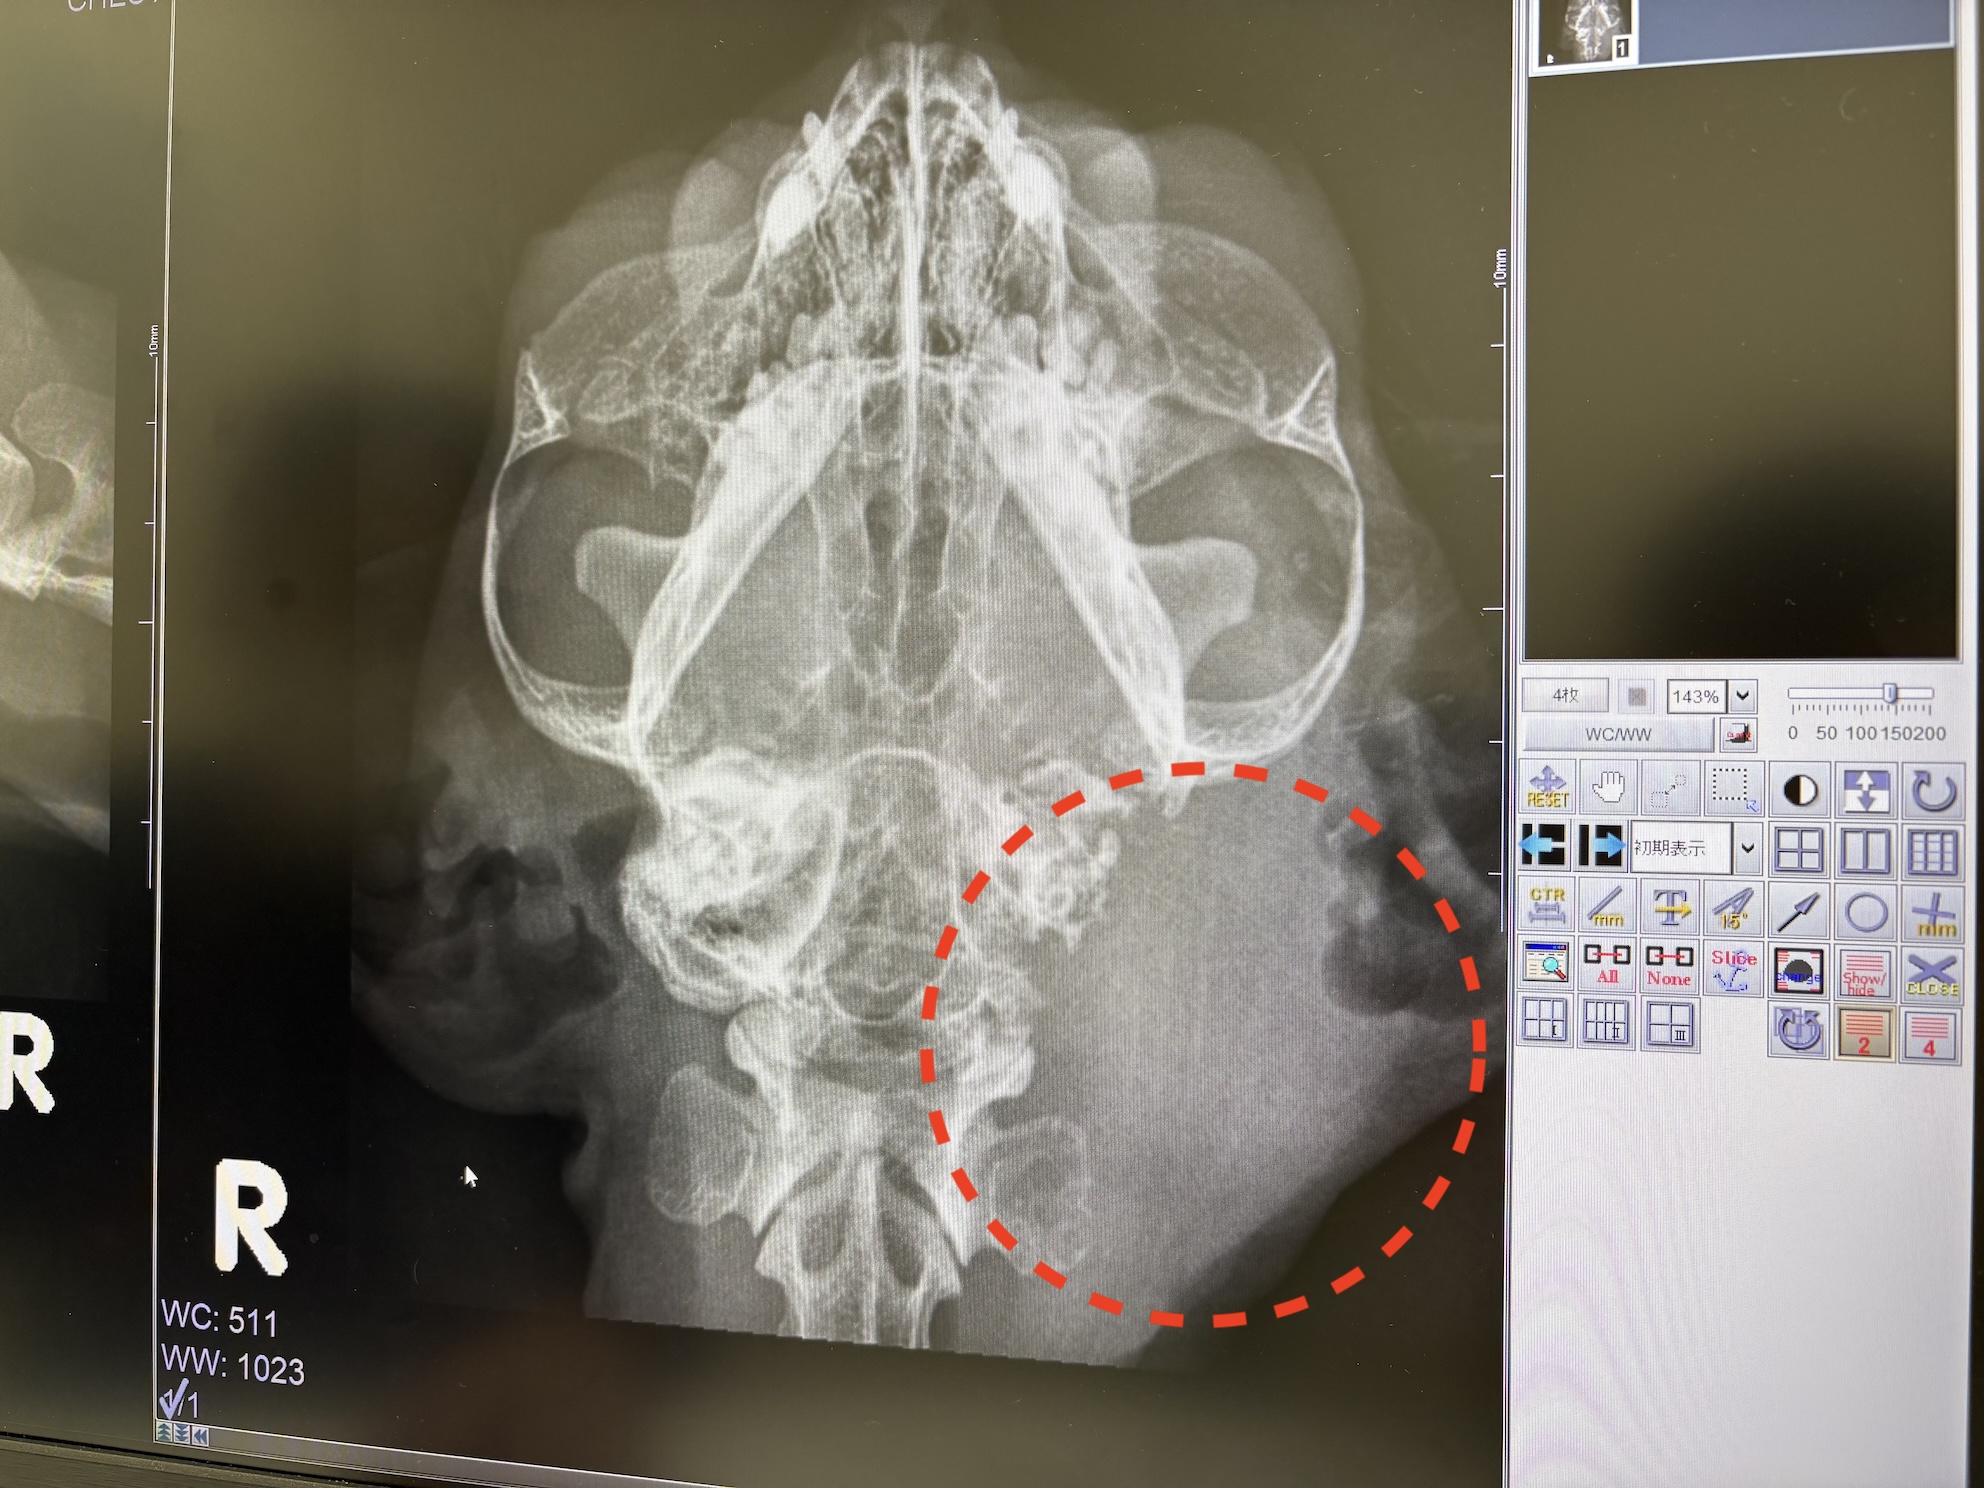

当日病院に着いて、まずはレントゲン検査と血液検査。

レントゲン検査の結果はあまり良くなく、

9月の猫ドックでも確認したように耳の奥の骨が溶けているのに加え、

耳の穴から内耳までの経路が何か(膿?腫瘍?)で塞がれてしまっているようだった。

CT検査の結果は、

悪性腫瘍(がん)の疑いが強いとのことだった。

耳から第一頚椎にかけて病変が広がっており、頭蓋骨も溶かして脳に到達しているような状態。

中耳~前庭にかけて組織が広範囲に壊れていて、神経疾患の原因はこれで間違いない。

実際の病変を採取して細胞診検査に回したが、

この段階で確定はできないものの炎症や白血球の増大が見られないため、

膿ではなく腫瘍の可能性が非常に高い。

大きなくくりでの症状としては中耳炎+前庭疾患に違いないが、

その原因が細菌性である可能性はほぼゼロ、ほぼ確実に腫瘍に由来するものだろう。